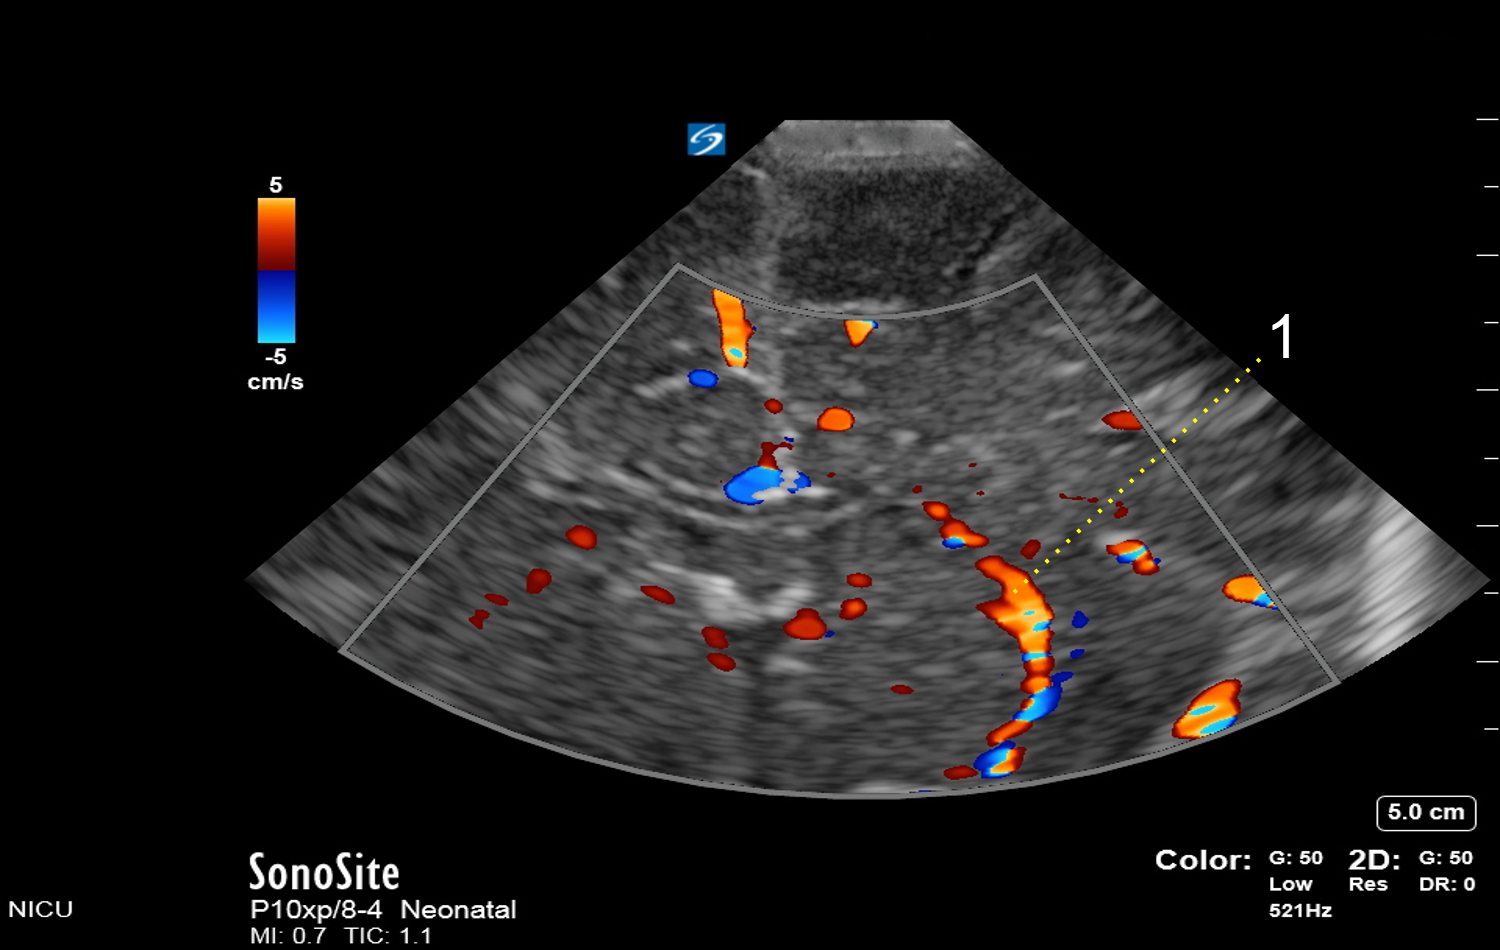

Neonatology Lenticulostriate Arteries Image

Lenticulostriate Arteries